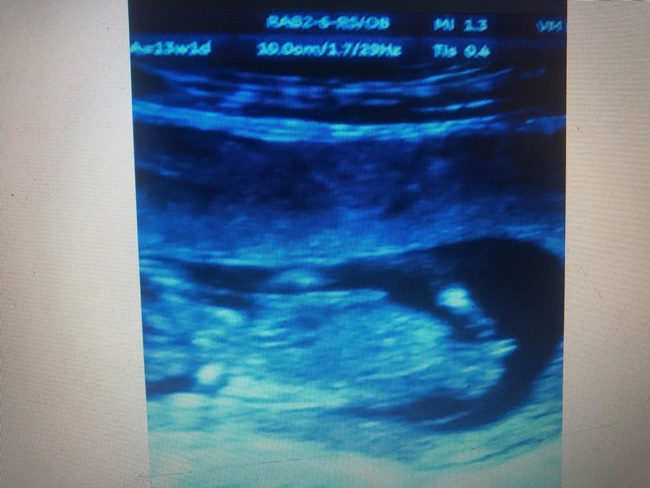

"Bu haftalarda bebegin cinsel organi genital tüberkül seklindedir farklilasarak ya kiz yada erkek organina donusecek bi yapi seklindedir ve ultrasonda bu genital tüberkül bebekle olan acisina bakarak paralelse kiz yukari bakiyorsa erkek olarak ancak %90;lik bir varsayimda bulunabiliriz.

2;nci haftayi beklemek durumundasiniz 2;nci haftada arti bu genital tüberkül degil genital organ olacaktir ama bu haftalara gelene kadar anneler arasinda cesitli soylentiler ve inanislar vardir cin takvimine bakarak yada karnin sekline bakarak, yedigine ictigine bakarak veya karin bolgesine yuzuk tutarak anlamaya calisirlar. Ama dedigimiz gibi karisikligi ortadan kaldirmak adina 16nci haftadan once hicbir ultrasonografi, cihazi bebegin cinsiyetini %100 oraninda belirleyemez.